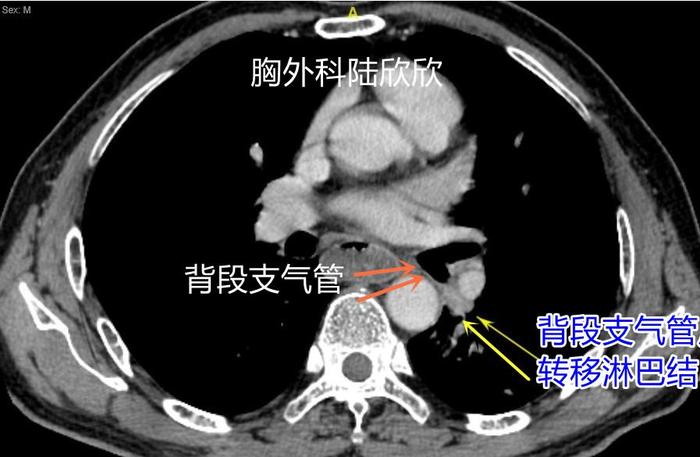

上图,背段支气管后方,可见一枚转移淋巴结,术后的病理证实。

术中看见的背段支气管旁淋巴结虽然看起来不像是转移,但是病理切片显示为转移。所以左下肺癌的肿瘤TNM分期是T2BN1M0。病人的肿瘤分期:IIB期。处于中期肿瘤的状态